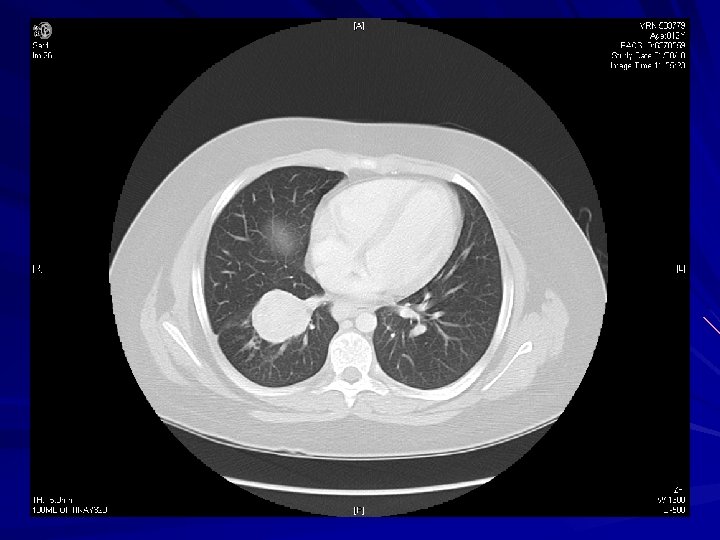

Diagnosis CXR – – 75% have abnormal CXR Round/ovoid mass 2 -5 cm Hilar or perihilar CT chest – 5 -20% have mediastinal or hilar LAD Bronchoscopy – 75% amenable to bx (centrally located) – Intact overlying bronchial epithelium Peripheral lesions: CT-guided bx/aspiration vs operative resection

Typical Appearance on CXR/CT

Typical Appearance on CT